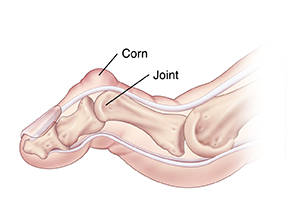

Rigid hammertoes

Rigid hammertoes are fixed (not flexible). You can't straighten the buckled joints. Corns, pain, and loss of function may be more severe with rigid hammertoes than with flexible ones.

| Rigid hammertoe. |